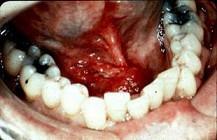

男,40岁,发现右侧口底部有一核桃大小质硬肿块(如图),触诊浸润已过中线。右侧颌下可扪及2个肿大淋巴结,黏连;左侧未扪及明显肿大淋巴结。关于颈部淋巴结的处...

问题 男,40岁,发现右侧口底部有一核桃大小质硬肿块(如图),触诊浸润已过中线。右侧颌下可扪及2个肿大淋巴结,黏连;左侧未扪及明显肿大淋巴结。关于颈部淋巴结的处理,以下哪项最佳 ( )

选项 A.双侧功能性颈淋巴清扫术 B.双侧根治性颈淋巴清扫术 C.右侧根治性颈淋巴清扫术 D.右侧根治性颈淋巴清扫术+左侧功能性颈淋巴清扫术 E.右侧功能性颈淋巴清扫术

答案 D